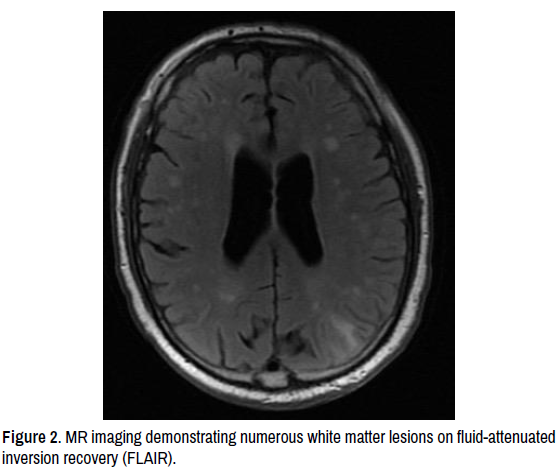

We report the case of a 69-year-old man who presented with acute confusion following a prodrome of frontal throbbing headaches for a few days prior. He had a notable background of ulcerative colitis, prostate cancer (locally extensive with no lymph node involvement), atrial fibrillation, hypertension, remitting psoriasis and hypertension. Initial CT imaging of the brain showed no acute changes, and a presumptive diagnosis of delirium was made given a mildly raised neutrophil count (8.3 × 109/L [normal range 2.0-7.5]), although all other basic laboratory investigations were normal. He was discharged from hospital but readmitted the following week with worsening confusion. MR imaging of the head had revealed a new large left parietal haemorrhage not present in the prior CT scan, as well as multiple small infarcts throughout the cortex bilaterally, innumerable microhaemorrhages and cortical subarachnoid blood (Figures 1-4).

vasculitis-numerous

Figure 2. MR imaging demonstrating numerous white matter lesions on fluid-attenuated inversion recovery (FLAIR).